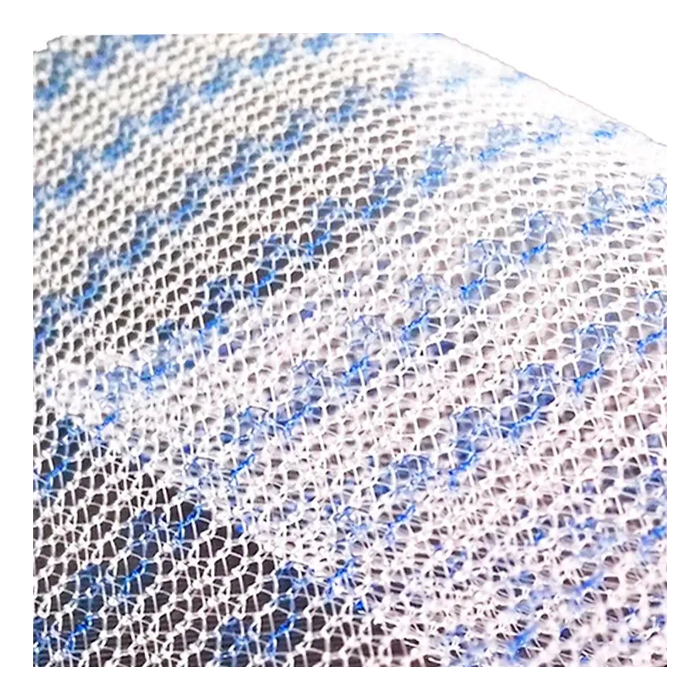

Эндопротез-сетка ЭСФИЛ — это современный, высококачественный хирургический имплантат, предназначенный для восстановительной и пластической хирургии. Изделие производится из инертного медицинского полипропилена, что обеспечивает его биосовместимость и надежную интеграцию в ткани организма. Сетка стандартного размера 30х30 см является универсальным решением для широкого спектра оперативных вмешательств, где требуется укрепление или замещение мягких тканей.

Ключевым преимуществом сетки ЭСФИЛ от «Линтекс» является ее макропористая структура. Это позволяет тканям пациента свободно прорастать через ячейки имплантата, формируя прочный соединительнотканный каркас и минимизируя риск осложнений, таких как отторжение или хроническая боль.

- Отличная интеграция: Макропористая структура способствует быстрому и полноценному прорастанию соединительной ткани, надежно фиксируя имплантат.

| Структура | Макропористая, монофиламентная или мультифиламентная (уточняется у производителя для конкретной модификации) |